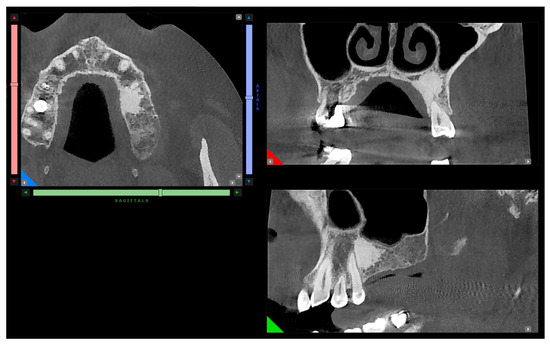

The patient was sent to the oral surgery specialist, who recommended the second-level X-ray examination (CBCT) due to the diagnostic doubt in the panoramic X-ray, thus involving a third specialist, the radiologist. The 3D exam was performed by an oral and maxillofacial center with a cone beam CT scanner with low-dose ionizing radiation, isotropic volume, and a 12 cm field. Axial, panoramic, and cross-section images (dental scan modality) were obtained by multiplanar reconstruction. Image dimensions were real to give the possibility of thickness and distance measurement. A three-dimensional X-ray showed a bone island of juxtacortical hyperdensity and defined edges in the premolar region of the left maxilla (Figure 3).

Figure 3.

Axial, sagittal, and paracoronal view of the hyperdense finding in CBCT examination.